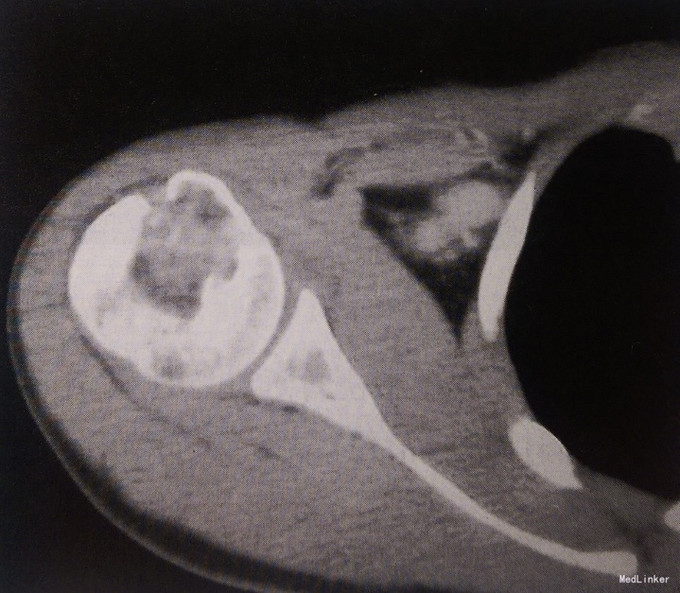

男性,21岁,右肩关节酸胀不适1月余。余无异常。

查体肩关节活动正常,无红肿。 影像学表现:CT示右侧肱骨头骨性关节面下可见囊状膨胀性骨质破坏,病灶内部密度不均匀,隐约可见点条状高密度钙化影。边缘分叶状,周边可见硬化缘,无明显骨膜增生和软组织肿胀。

诊断:右肱骨软骨母细胞瘤 治疗:手术治疗

本病需要与巨细胞瘤鉴别,后者多发生于骨成熟后的骨端,大多膨胀较骨母细胞瘤明显,且病灶内多有骨间隔,瘤内无钙化,与骨母细胞瘤不同。透明细胞软骨肉瘤亦可表现为边界清楚的轻度膨胀性病变,且可发生于骨骺闭合之前,但表面骨皮质常被破坏,并出现骨膜反应。